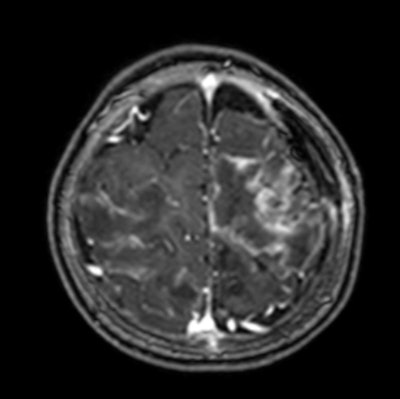

Contrast-enhanced T1-weighted MRI scan shows multiple abscesses due to free-living amebiasis (Balamuthia mandrillaris).

Neurocysticercosis is still prevalent but is decreasing in Peru, whereas free-living amebiasis is less common but has a rising prevalence and is often fatal without treatment. Toxoplasmosis remains a significant congenital infection in Latin America, and it's important to be aware of hydatid disease, malaria, toxocariasis, and strongyloidiasis.

Free-living amebiasis is a growing concern, being rapidly progressive and often fatal without early intervention. Congenital toxoplasmosis remains prevalent, and the severe features are more prevalent in Latin America.

Radiologists play a vital role by making a timely diagnosis using MRI, improving outcomes, and guiding treatment. "Our call to action should be advocacy for improved sanitation, healthcare access, and education to combat these infections," he said.